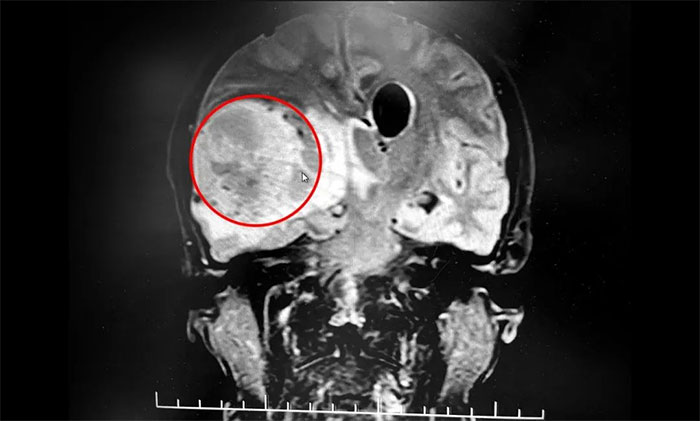

▲ MRI检查,提示鸭蛋大小脑肿瘤

急行头颅MRI检查,提示:右侧额颞叶见团块状不均匀异常信号影,周围见明显水肿信号,增强后呈明显花边样强化,壁薄厚不均,内壁欠光滑,中央区未见强化,病灶大小约5.6*4.4*5.1cm,侧脑室受压及脑干、第三脑室变窄,中线结构向左移位,左侧侧脑室扩大。考虑为高级别脑胶质瘤伴脑疝形成。

患者颅内有一枚鸭蛋大小的脑肿瘤,病情进展迅速,已因颅内压增高出现脑疝。若脑干等重要脑组织持续受压,可在短时间出现功能衰竭,危及患者生命。